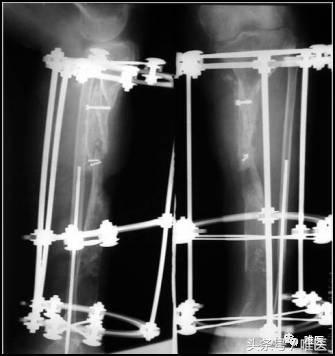

一期:左胫骨全环外架固定,远端截骨,术后骨段逐渐滑移,克服骨缺损。

先一期截骨,使用外固定架进行骨段滑移。

当两骨断段逐渐靠近接触后,二期行断端清理和修整,造成新鲜骨创面,并使断端良好对合,同时植骨,继续外架固定。